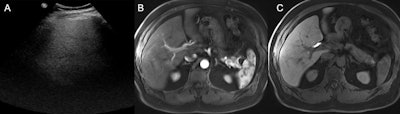

Images in a 64-year-old obese man (body mass index, 35.2, calculated as weight in kilograms divided by height in meters squared) with metabolic dysfunction–associated steatotic liver disease who underwent hepatocellular carcinoma screening demonstrate discordant quality between MRI and ultrasound (US). (A) Poor liver visualization was noted at US (severe limitations [US-C]), with severe beam attenuation and shadowing, resulting in most of the liver not being visualized. (B, C) The quality of the MRI scans was excellent, with (B) minimal motion in the arterial phase on the postcontrast T1-weighted image and (C) no limitations on the delayed hepatobiliary phase image in the axial plane. Images and caption courtesy of the RSNA.Images in a 64-year-old obese man (body mass index, 35.2, calculated as weight in kilograms divided by height in meters squared) with metabolic dysfunction–associated steatotic liver disease who underwent hepatocellular carcinoma screening demonstrate discordant quality between MRI and ultrasound (US). (A) Poor liver visualization was noted at US (severe limitations [US-C]), with severe beam attenuation and shadowing, resulting in most of the liver not being visualized. (B, C) The quality of the MRI scans was excellent, with (B) minimal motion in the arterial phase on the postcontrast T1-weighted image and (C) no limitations on the delayed hepatobiliary phase image in the axial plane. Images and caption courtesy of the RSNA.